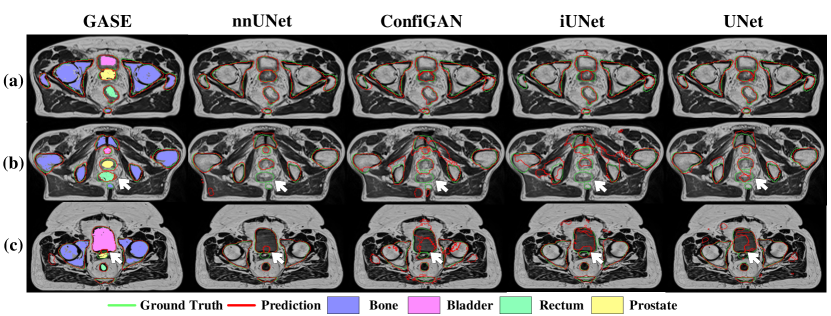

Refer to caption

Figure 6: Illustration of segmentation results for three cases. a) Easy case when all classes have distinct features. b) Difficult case when all classes have intricate features, especially for the imbalanced classes like the rectum and prostate. c) Data shifting case when the patient has a large amount of abdominal fat and abnormal bladder contrast. Segmentation outlines are drawn in red (Prediction) and green (GT).

Tab. 2 shows the quantitative results for the chosen models. GASE performs the best in terms of DSC and HD for non-rigid components such as the bladder, prostate and rectum segmentation. It performs slightly worse than nnUnet on HD and does not perform as well as nnUnet for the rigid component such as bone. The reason is that fine-grained features of the bone are relatively consistent across all training samples, which limits the features that could be diversified during image synthesis, hence, the segmentation accuracy of the bone. The visualisation of segmentation results is also demonstrated in Fig. 6. As shown in Fig. 6a, all models achieve accurate segmentation results when all classes have distinct features such as density, contrast and shape from each other. However, as the features among classes become more intricate, for example, the smaller bladder, multiple sections of bone, and similar features between rectum and prostate, shown in Fig. 6b. GASE is the only model that can consistently produce accurate label maps for all classes, especially the rectum, which is missing in all other models’ results. Moreover, it is found that GASE performs substantially better than other models for one validation fold whose testing set contains one case with extreme data shifts compared to the corresponding training set. The results are displayed in Fig. 5. As demonstrated in Fig. 6c, the extreme case has an abnormal bladder contrast with substantially more body fat compared to images in a) and b), and only GASE and nnUnet could segment all classes properly. However, by comparing the segmented prostate from both models, GASE successfully mitigates the misclassified prostate within the bladder. The nnUnet, on the other hand, falsely segments a large portion of the bladder as the prostate due to the unseen bladder contrast. Both quantitative and qualitative results indicate that our GASE is more generalisable to distribution shifts than other models.